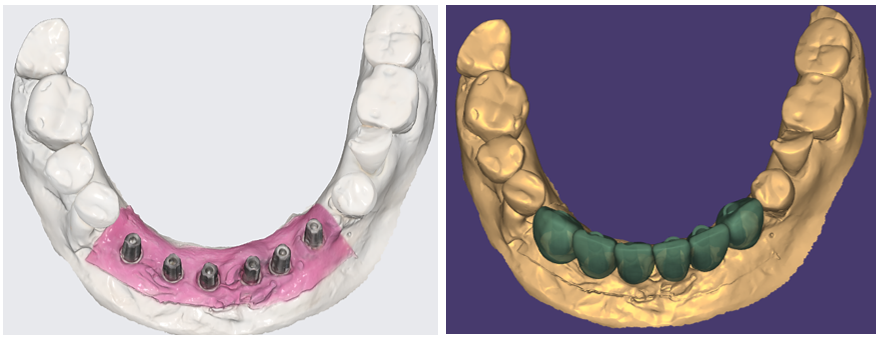

O planejamento reverso em Implantodontia assume importante papel no posicionamento 3D dos implantes. Nesse sentido, relatamos esse caso de ausência dos dentes anteriores inferiores (31/32/33/41/42/43) de um paciente usuário de prótese parcial removível que tinha o desenho de usar uma prótese fixa sobre implantes, como ilustrado nas imagens abaixo.